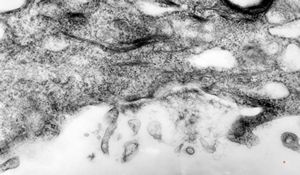

F, 39y. | collagenous and elastin fibers from corium